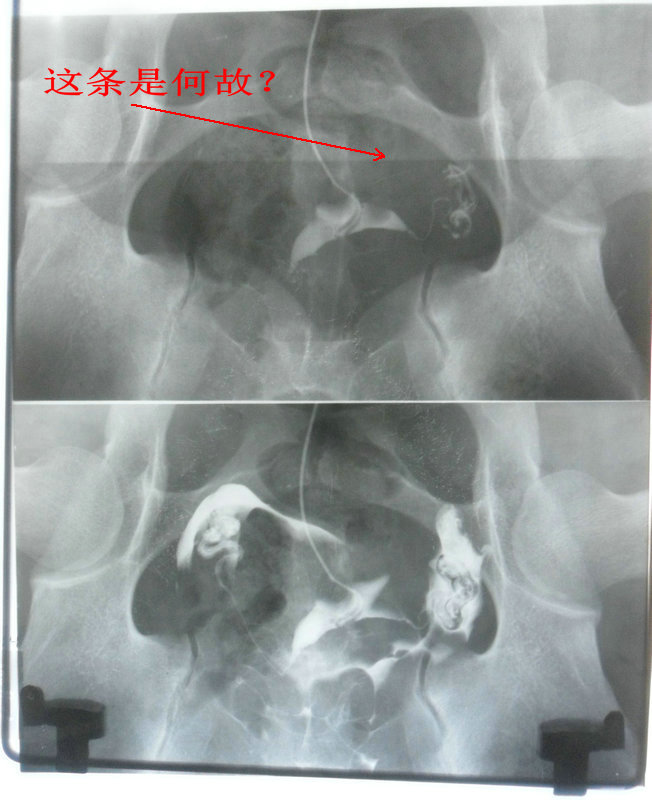

点全片正常;点上下分片第1张有明显的边沿整齐的影条;点左右分片时2张都有;点4分片时4张都有。

左右2分片时:

左右2分片.JPG

4分片时:

4分片.JPG

考虑点片分格板两块都有问题,铅当量不够而点片KV高。可以在分格铅板四个周边贴上铅号码,如果号码在点片后能显示出来说明有问题。铅当量够时,分格板挡住了射线,所贴的铅号码是不可能显示的。

上下2分片子的第二张没有,可能问题就出在点片分格的铅板上下方向铅当量不够。

我仔细观察过,上下分片时,分格的铅板没有移动,而是后面的胶片第一張时先在下面,曝光后,要照第二张时,胶片先上移动到位,才能再曝第二次光。

分格的铅板分片时没动,用的是同样状态。

千伏降5kv后,影条明显减弱;降10kv后,影条基本看不到了。但显影时间延长2倍,对比度差。